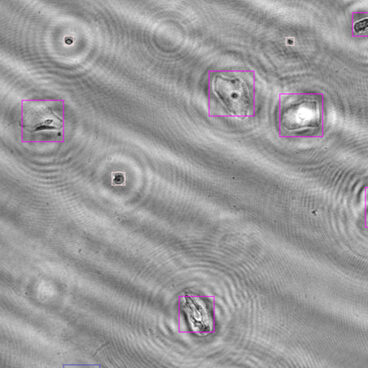

Particle detection

Digitally classifying urine sediment structures

Our module identifies a wide range of particle types typically assessed in urine microscopy. Imaging and classification are performed without the need for staining, calibration or subjective review.

The current AI model is trained to detect and classify:

- Red and white blood cells

- Hyaline and granular casts

- Crystals (e.g., struvite, calcium oxalate)

- Squamous and transitional epithelial cells

The classification range can be adapted or extended based on specific diagnostic requirements. Whether you need additional structures or new sample types, the underlying pipeline is built to grow with your use case.